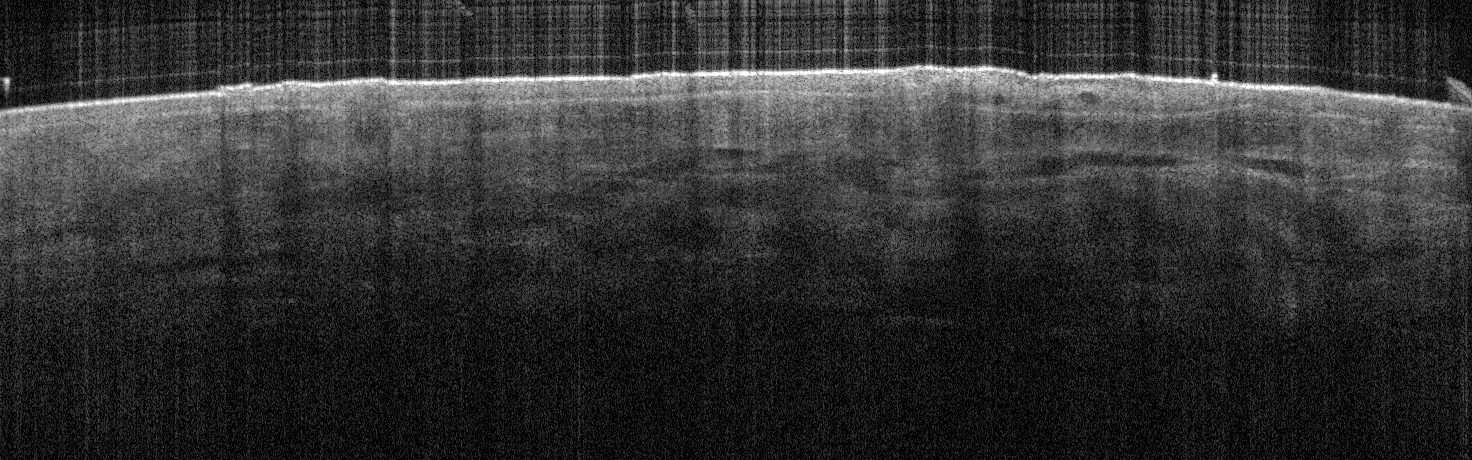

VA34: Right Temple, Adjacent, Normal

- Note normal hair follicle presentation